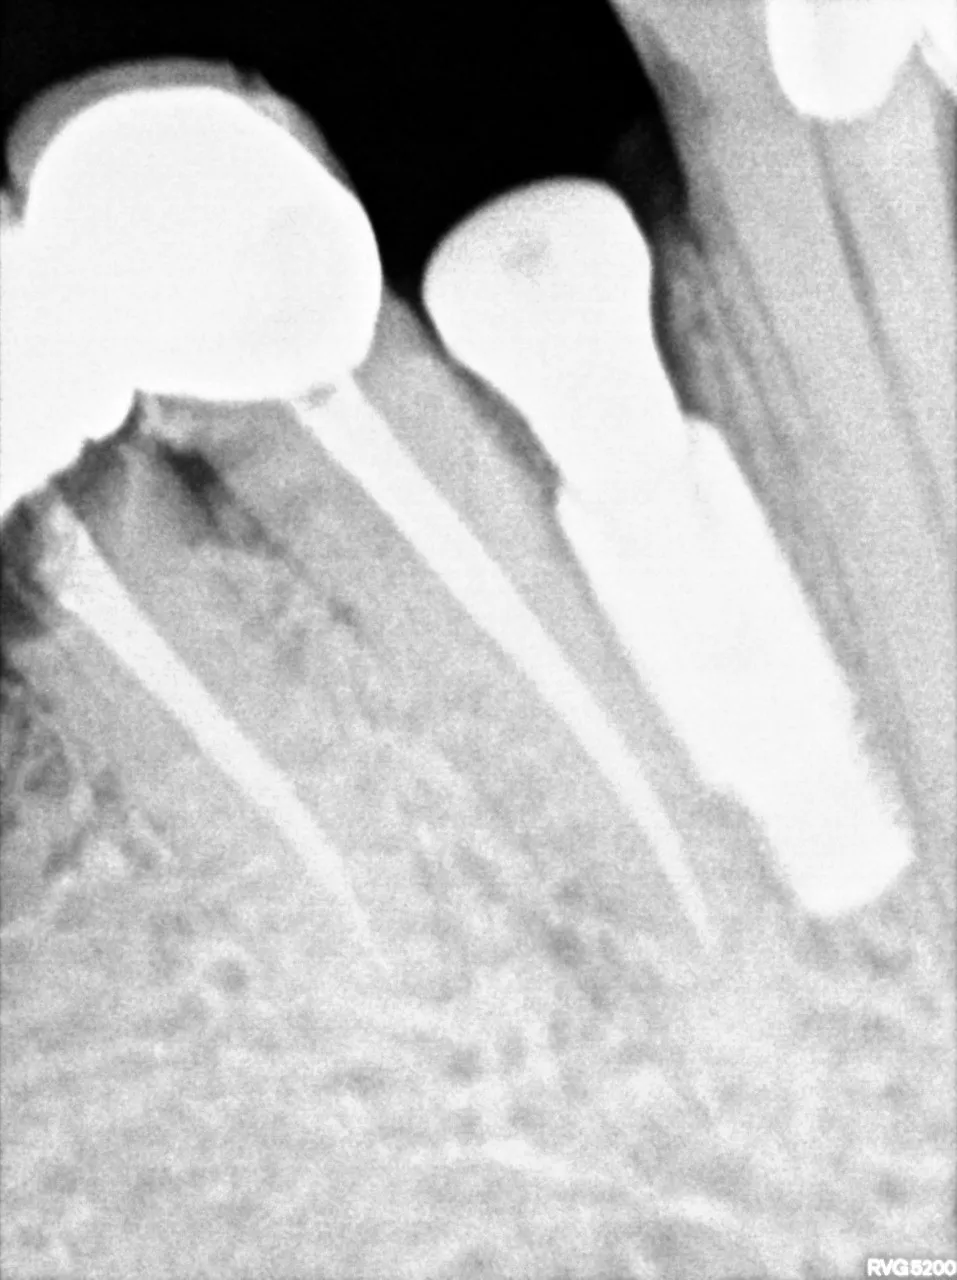

2: Precision-Guided Implant Placement

-

- Six titanium implants were placed using computer-guided navigation, ensuring optimal positioning.

- Strategic site selection leveraged areas of highest bone density for maximum integration and stability.

- A minimally invasive approach reduced surgical trauma, supporting faster healing.